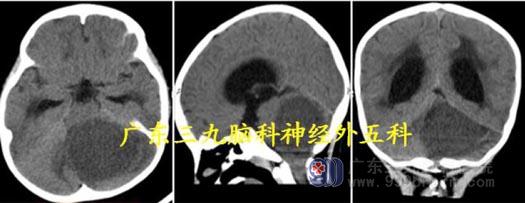

头颅MR:左侧小脑示一类圆形占位性病变,小囊状坏死区呈低信号,增强后病变明显不均匀强化,范围约为4.6cm×4.1cm×4.5cm,周围示片状长T1 长T2 水肿信号影。考虑毛细胞星形细胞瘤?

头颅CT:左侧小脑示一类圆形占位性病变,呈低密度影,幕上脑积水(中度)。